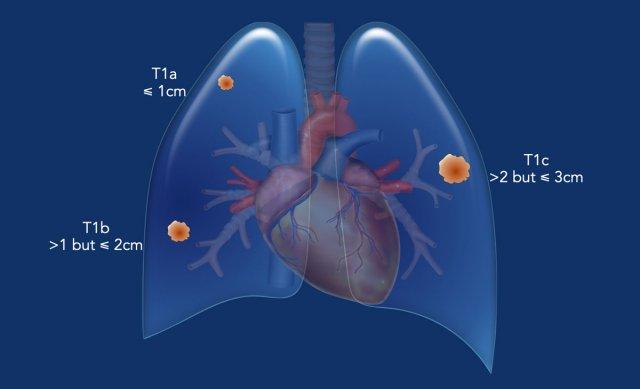

Khối u T1 (≤ 3 cm, được bao quanh bởi nhu mô phổi/màng phổi tạng, hoặc nằm ở phế quản thùy hay xa hơn về phía ngoại vi).

- T1mi: Ung thư biểu mô tuyến xâm lấn tối thiểu.

- T1a: Khối u có kích thước lớn nhất ≤1 cm.

- T1b: Khối u có kích thước lớn nhất >1 cm nhưng ≤2 cm.

- T1c: Khối u có kích thước lớn nhất >2 cm nhưng ≤3 cm.

Ví dụ:

Một khối u T1 điển hình ở thùy dưới phổi trái (23 mm, cT1c), được bao quanh hoàn toàn bởi nhu mô phổi.